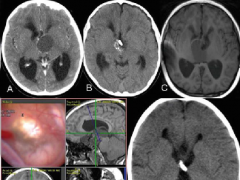

颅咽管瘤是儿童下丘脑和鞍上区较常见的病变,外胚叶形成的颅咽管残余的上皮细胞,发展起来的一种常见的胚胎残余组织肿瘤,是颅内较常见的先天性肿...

颅咽管瘤(CP)是一种少见的鞍区和鞍旁区上皮性肿瘤,组织学级别较低(WHO级)。它们约占成人全部原发性颅内肿瘤的1%,占儿童的1.2-4%,是后者较常见的鞍区肿瘤...

颅咽管瘤是什么?不同解剖部位的颅咽管瘤可以是囊性、实性或囊性,有些肿瘤可能有一些钙化。 颅咽管瘤发生的主要部位是鞍区,也可以在鞍区、鞍区、...